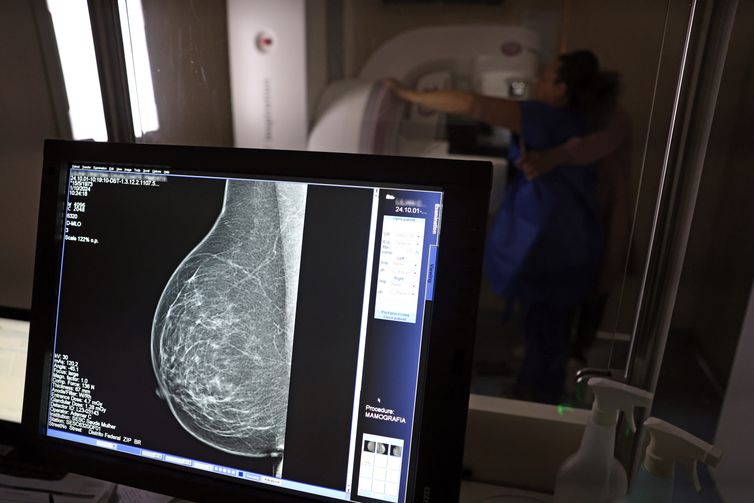

Câncer de mama é uma das doenças que mais afetam mulheres no Brasil, impactando não apenas a saúde física e emocional, mas também a capacidade de trab

Outubro Rosa: como receber o auxílio-doença em tratamento de câncer

© José Cruz/Agência Brasil